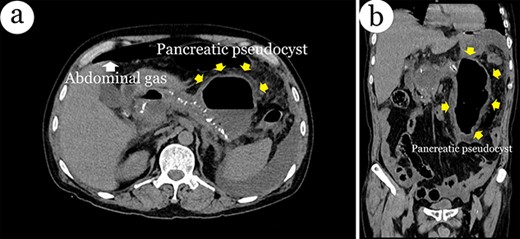

On admission, computed tomography (CT) scans revealed a significant amount of free abdominal fluid and identified the presence of extraluminal gas showed signs of GI perforation, as well as intra-cholecyst gallstones (Fig. 1). The pancreatic parenchyma has many calcified nodules. The patient was transferred to our emergency operating room with symptoms of septic shock. Subsequently, the abdominal cavity was aspirated with 1248 mL of the infected fluid. However, we found an entire GI tract and a rupture in the pseudocyst wall filled with a turbid fluid, similar to intra-abdominal fluid (Fig. 2a and b). This PP was encircled by the jejunal loop, digestive mesentery and splenic flexure of the colon, all located on the right side of the abdomen. The diametric pseudocyst was extremely large and connected with the intestinal lumen. We performed a partial resection of the pseudocyst wall surface electrocautery inside the lumen of the PP (Fig. 3).

Computerized tomography of the abdomen with intravenous contrast shows a massive pseudocyst within the left side of the abdomen, extraluminal gas and gallstones in axial plane (a) and coronal plane (b).